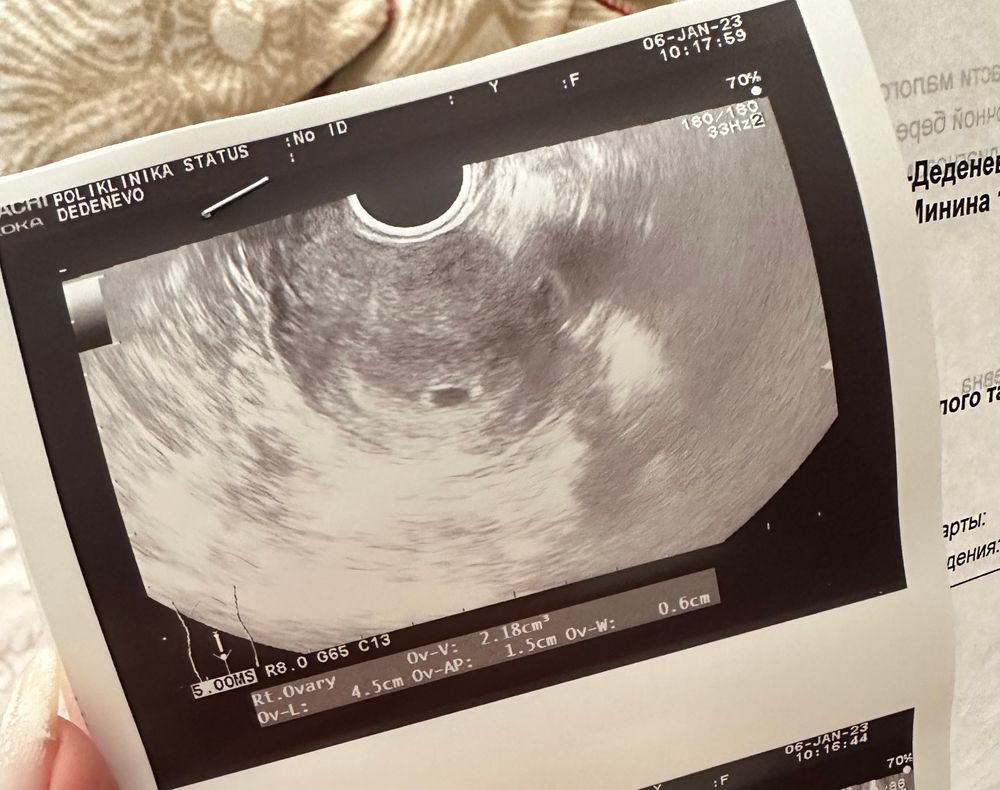

Какая ж маленькая, но уже такая любимая точечка! Расти детка, всего лишь 6мм большой всеобъемлющей любви 😍

Сегодня 4.6 недели, эндометрий 18мм, жт 28мм🤞🏻